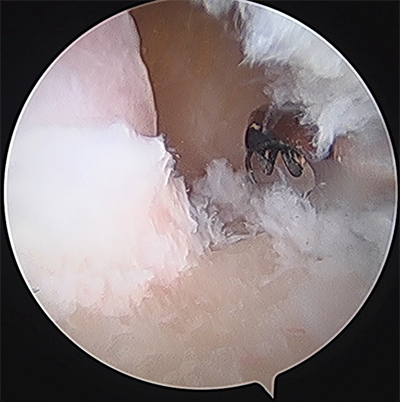

内視鏡下のドリリング

骨棘の切除

内視鏡下の遊離体摘出や骨棘切除、炎症組織である関節滑膜の切除を行います。